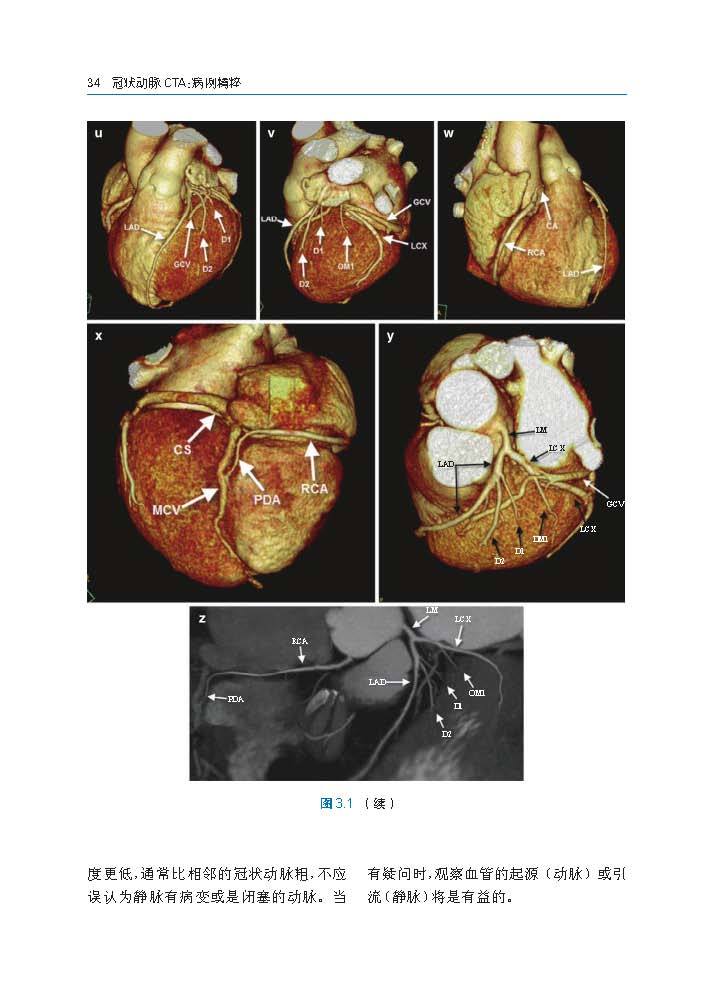

本书涵盖多种心脏冠状动脉病例,每个病例都包括精细的CTA图像、简短的病史报告、检查、诊断、讨论、经验和教训,分析正常冠状动脉解剖、先天冠状动脉发育异常、冠状动脉性疾病、经皮冠状动脉治疗、心脏外科血运重建术后改变,以及除冠状动脉以外的心-胸血管发育异常。在第1版的基础上,新增关于心脏CT的操作及报告原则、心肌病、儿童心脏病、急诊心脏CT应用、源自CT的血流储备分数的章节。本书旨在帮助心血管及影像科医生、心脏内科医生和心胸外科医生了解与冠状动脉CTA的临床及后续干预的一系列问题,图文并茂,内容翔实,具有很强的实用性。

本书涵盖多种冠状动脉疾病CTA病例。其影像分析包括正常冠脉解剖、先天冠脉发育异常、冠状动脉性疾病、经皮冠状动脉治疗、心外科血运重建术后改变,以及除冠状动脉以外的其他心胸血管发育异常。